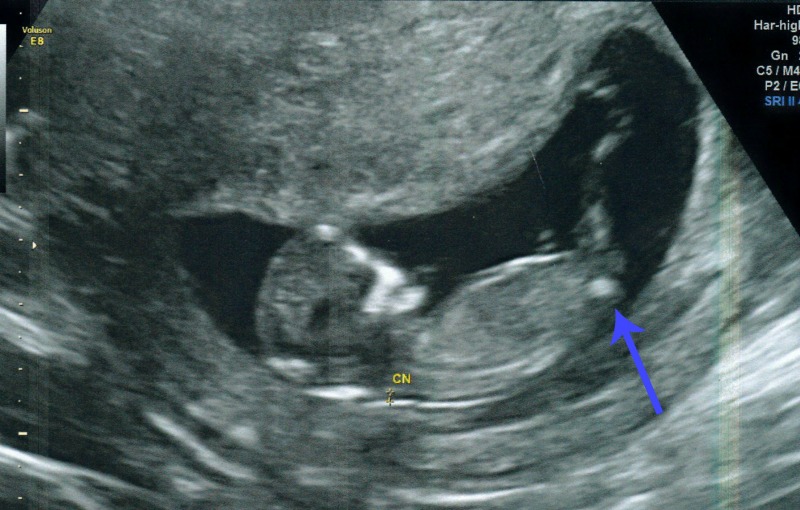

- Several times I saw a clear, long white nub... it was very straight and seemed longer than any of the other nub pictures on here. Not sure what long nub means?

- Numerous times I saw, in profile view, what looked like two white parallel lines. Both lines were shorter than the nub mentioned above but in the same place.

Unfortunately I dont have a clear picture of them but in the following picture you can see them but a bit fuzzy;